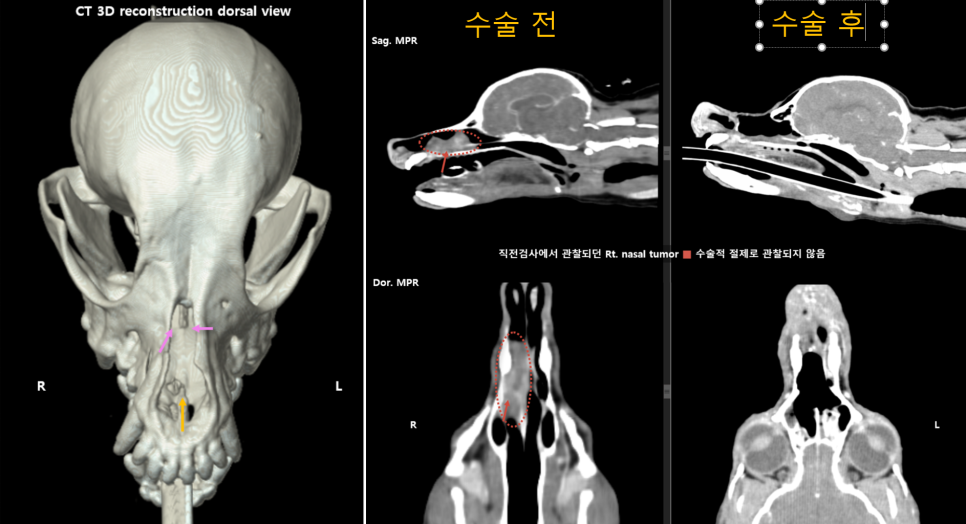

- CT촬영 결과: 푸들 강아지 환자는 우측 비강(코)에 직경 3Cm 크기의 종양이 확인되었습니다.

울산 에스동물병원 강아지 비강종양 환자의 CT 촬영

강아지 비강종양 수술은 육안으로 보이는 종양을 제거하는데 효과적이고, 수술 후 비강종양으로 인한 호흡불편을 줄이는데 도움을 줍니다. 본 푸들 환자는 수술 후 바로 CT촬영에서T에서 보이던 종양 조직이 제거된 모습이 확인됩니다. 비강종양 강아지 환자는 4일간 산소처치 및 집중 입원처치를 통해 한결 쉬워진 호흡이 가능한 것을 확인 후 보호자 곁으로 돌아갈 수 있었습니다.

비강 종양 수술 전 후 CT 비교영상 / 출처: 에스동물메디컬센터 울산점